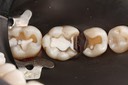

Kyle Chock#14 pre-op

Kyle Chock #14 caries removal

Kyle Chock #14 prep

Kyle Chock #14 finish